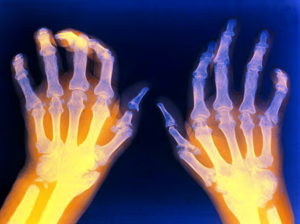

Метотрексат при ревматоидном артрите – основное лечение, избавляющее от симптомов и воспаления. Медленный эффект сохраняется на весь срок, пока идет прием препарата. Назначать средство имеет право только доктор, самостоятельное лечение приведет к массе нежелательных последствий. Ревматоидный артрит – специфическая патология, требующая длительного лечения. Аутоиммунный процесс уничтожения собственных здоровых тканей, запускающийся в организме часто по невыясненным причинам, негативно воздействует на суставы.

Помимо цитостатического эффекта лекарственное средство обладает противовоспалительным действием. Период ремиссии увеличивается, и суставы дольше не подвергаются разрушению. Течение заболевания замедляется, болевые ощущения беспокоят значительно реже, двигательная активность остается на прежнем уровне.

Опухоль, возникающая в пораженных суставах, исчезает, после чего движения становятся легче, пропадает скованность. Под защитное влияние препарата попадает хрящевая ткань, сухожилия связки. Впоследствии разрушение сустава останавливается, что поможет сохранить функциональность как можно дольше.